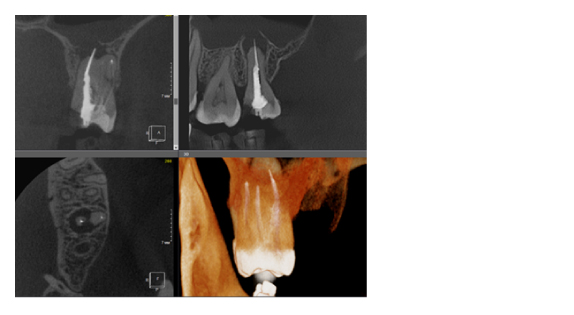

По сути воксель – это структурная единица изображения. Компьютерная томограмма состоит из вокселей, и их размер определяет качество снимка. Как правило, чем меньше FOV снимка, тем меньше и размер вокселя, а это, в свою очередь, делает изображение более качественным (рис. 3). Разные фирмы, производящие дентальные томографы пытаются конкурировать в размерах вокселя, особенно при больших зонах сканирования. Я стараюсь использовать два режима, как правило, это standart definition со средним размером вокселя и high definition с уменьшенным размером вокселя. Если намечается сложная эндодонтия, то, безусловно, high definition с минимальным значением вокселя будет крайне эффективно, но если у пациента огромное количество металла (циркон, металлокерамика и прочее) то порой именно стандартный размер вокселя помогает снизить количество артефактов и сделать изображение более читабельным.